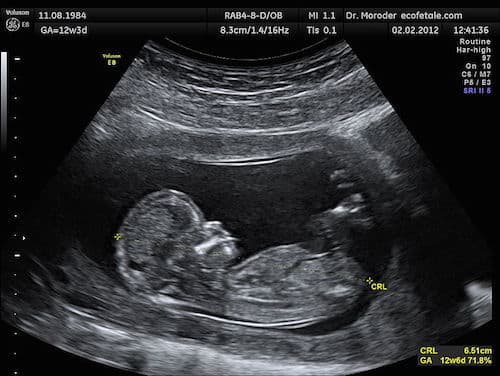

Photo: Ultrasound image of fetus at 12 weeks, by Wolfgang Moroder. (Own work) [CC BY-SA 3.0 or GFDL], via Wikimedia Commons.